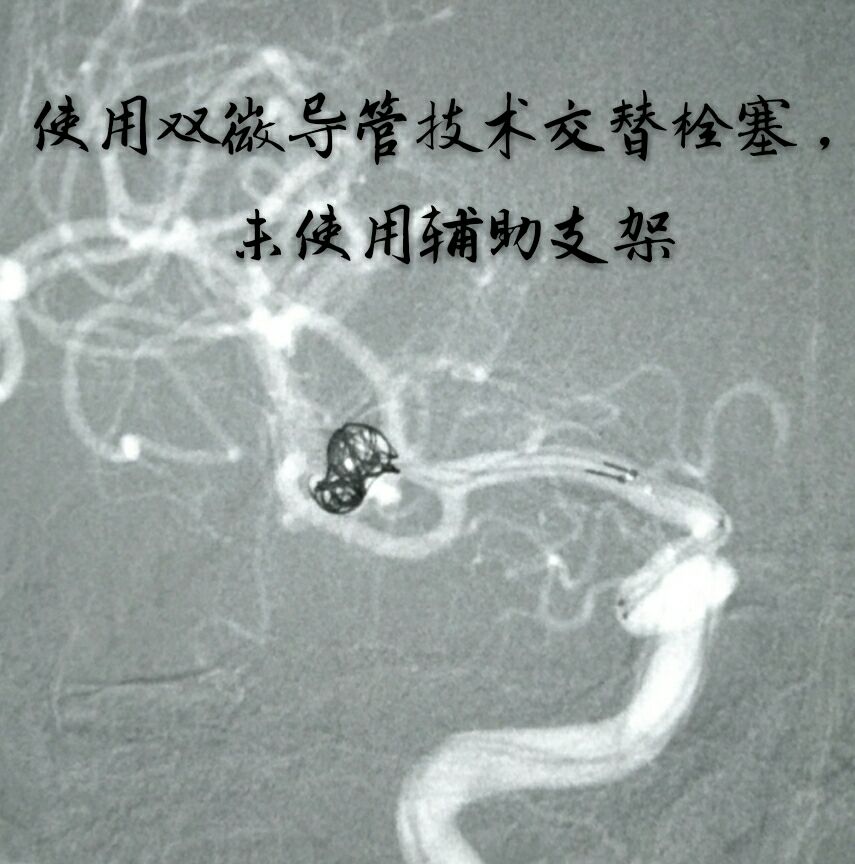

因瘤颈下方分支与动脉瘤关系密切,角度刁钻,而血管纤细,无法用辅助支架保护,术前做了详细、精准的计划,决定用双微导管技术栓塞

双微导管交替成栏栓塞,利用弹簧圈之间互相缠绕稳定弹簧圈